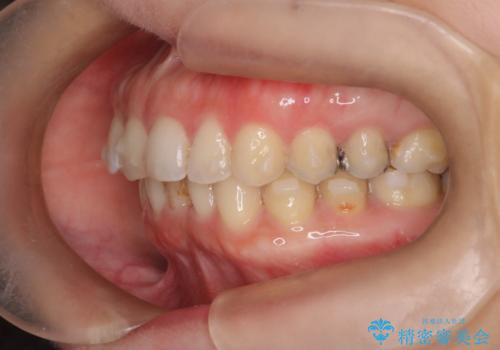

【下顎前歯の抜歯矯正】マウスピース矯正

- 下顎前歯の叢生を主訴に来院されました。

臼歯関係の状態から下顎前歯一本の抜歯を行う治療計画を立て、インビザラインを使用して治療を行いました。

今回の抜歯ケースはインビザラインでも綺麗に治ります。